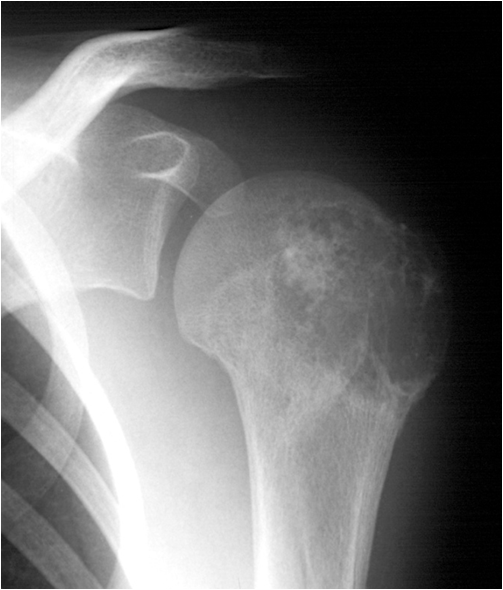

Another way to further characterize bone tumors is to search is looking at tumor associated matrix. Matrix is produced by osteoblasts and chondroblasts and usually is the basis for new bone or cartilage formation. Matrix produced by tumors is usually quite abnormal and does not ossify properly. The matrix produced by bone tumors may help to classify a lesion as cartilage producing tumor (enchondroma, chondrosarcoma, chondromyxoid fibroma, etc.) or bone-producing tumor (osteoma, osteoblastoma, osteosarcoma, etc.). Chondroid matrix tends to produce small punctate or swirled areas of calcification. Osseous matrix is dense and confluent. Some lesions show little or no calcification in their matrix (fibrous dysplasia, fibrosarcoma, malignant fibrous histiocytoma, solitary bone cyst, etc.).

Fig. 19. Chondrobastoma: An expansile lesion involving theepiphysis, physis and metaphysis of the humerus is depicted. The lucent lesion shows cortex destruction and spotty matrix calcifications.